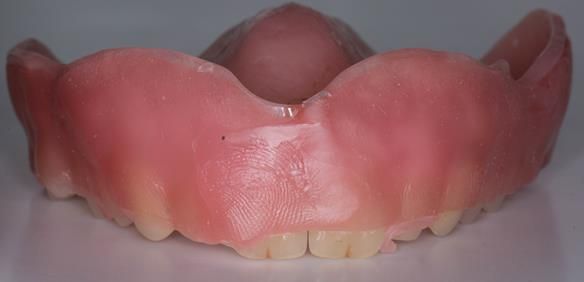

This newsletter describes in step by step detail the transition from acrylic based immediate dentures to metal based definitive dentures.

- Definitive dentures (Mk 2) – complete upper metal reinforced and lower cobalt chromium based partial of hygienic Scandinavian design to be made 9 - 12 months after extractions of all upper teeth and LR5 and LL4